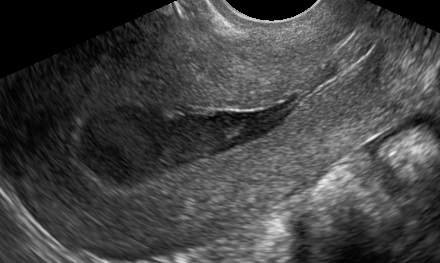

Complete cervical stenosis can be congenital or acquired, e.g. following conization. The condition is associated with amenorrhea, cyclical lower abdominal pain, and hematometra.

The risk of developing a complete cervical stenosis after conization is very low (< 1%) and is believed to be associated with estrogen-deficiency, since it is more often in postmenopausal and breast-feeding women (Koyama et al, 2014).